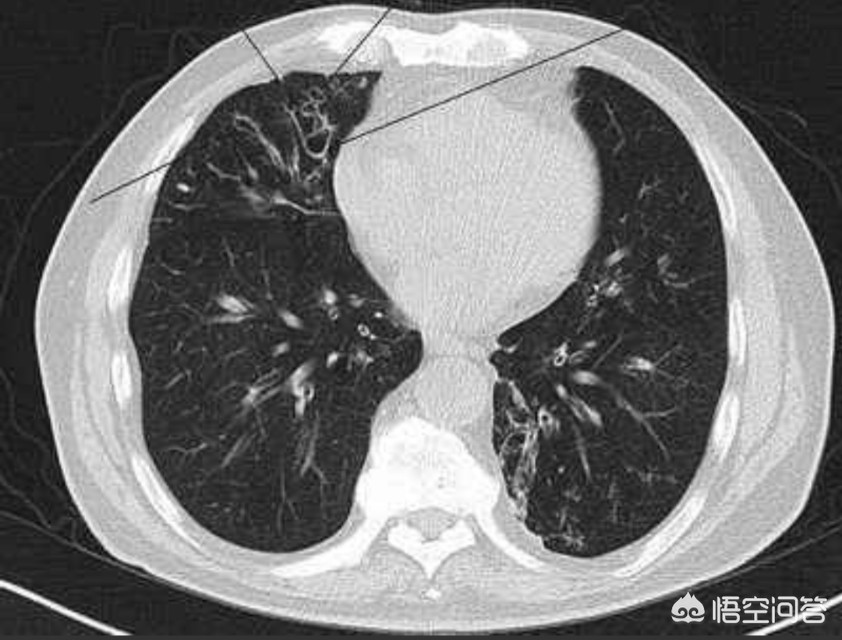

支气管扩张的诊断,X线检查有重要意义,支气管造影术可确诊,能明确支气管扩张的部位、性质和范围,为手术切除提供重要的资料。对造影剂过敏者可做胸部CT检查,超薄CT扫描是诊断支气管扩张的一项敏感检查方法。

诊断方面,除了症状(单靠症状并不可靠,很多其他病变也能引起相同的浓痰和咯血)外,主要靠影像学。

有了CT,尤其是能做高分辨CT(HRCT)后,诊断支扩变得相对容易很多,病人也没有痛苦了。

在HRCT上,支扩可分为柱状扩张,囊状扩张,混合型扩张等,标准通常为大于伴行动脉的直径,或者轻微的支扩,仅仅表现为失去逐渐变细的趋势,使得早期诊断轻微的支扩称为可能。